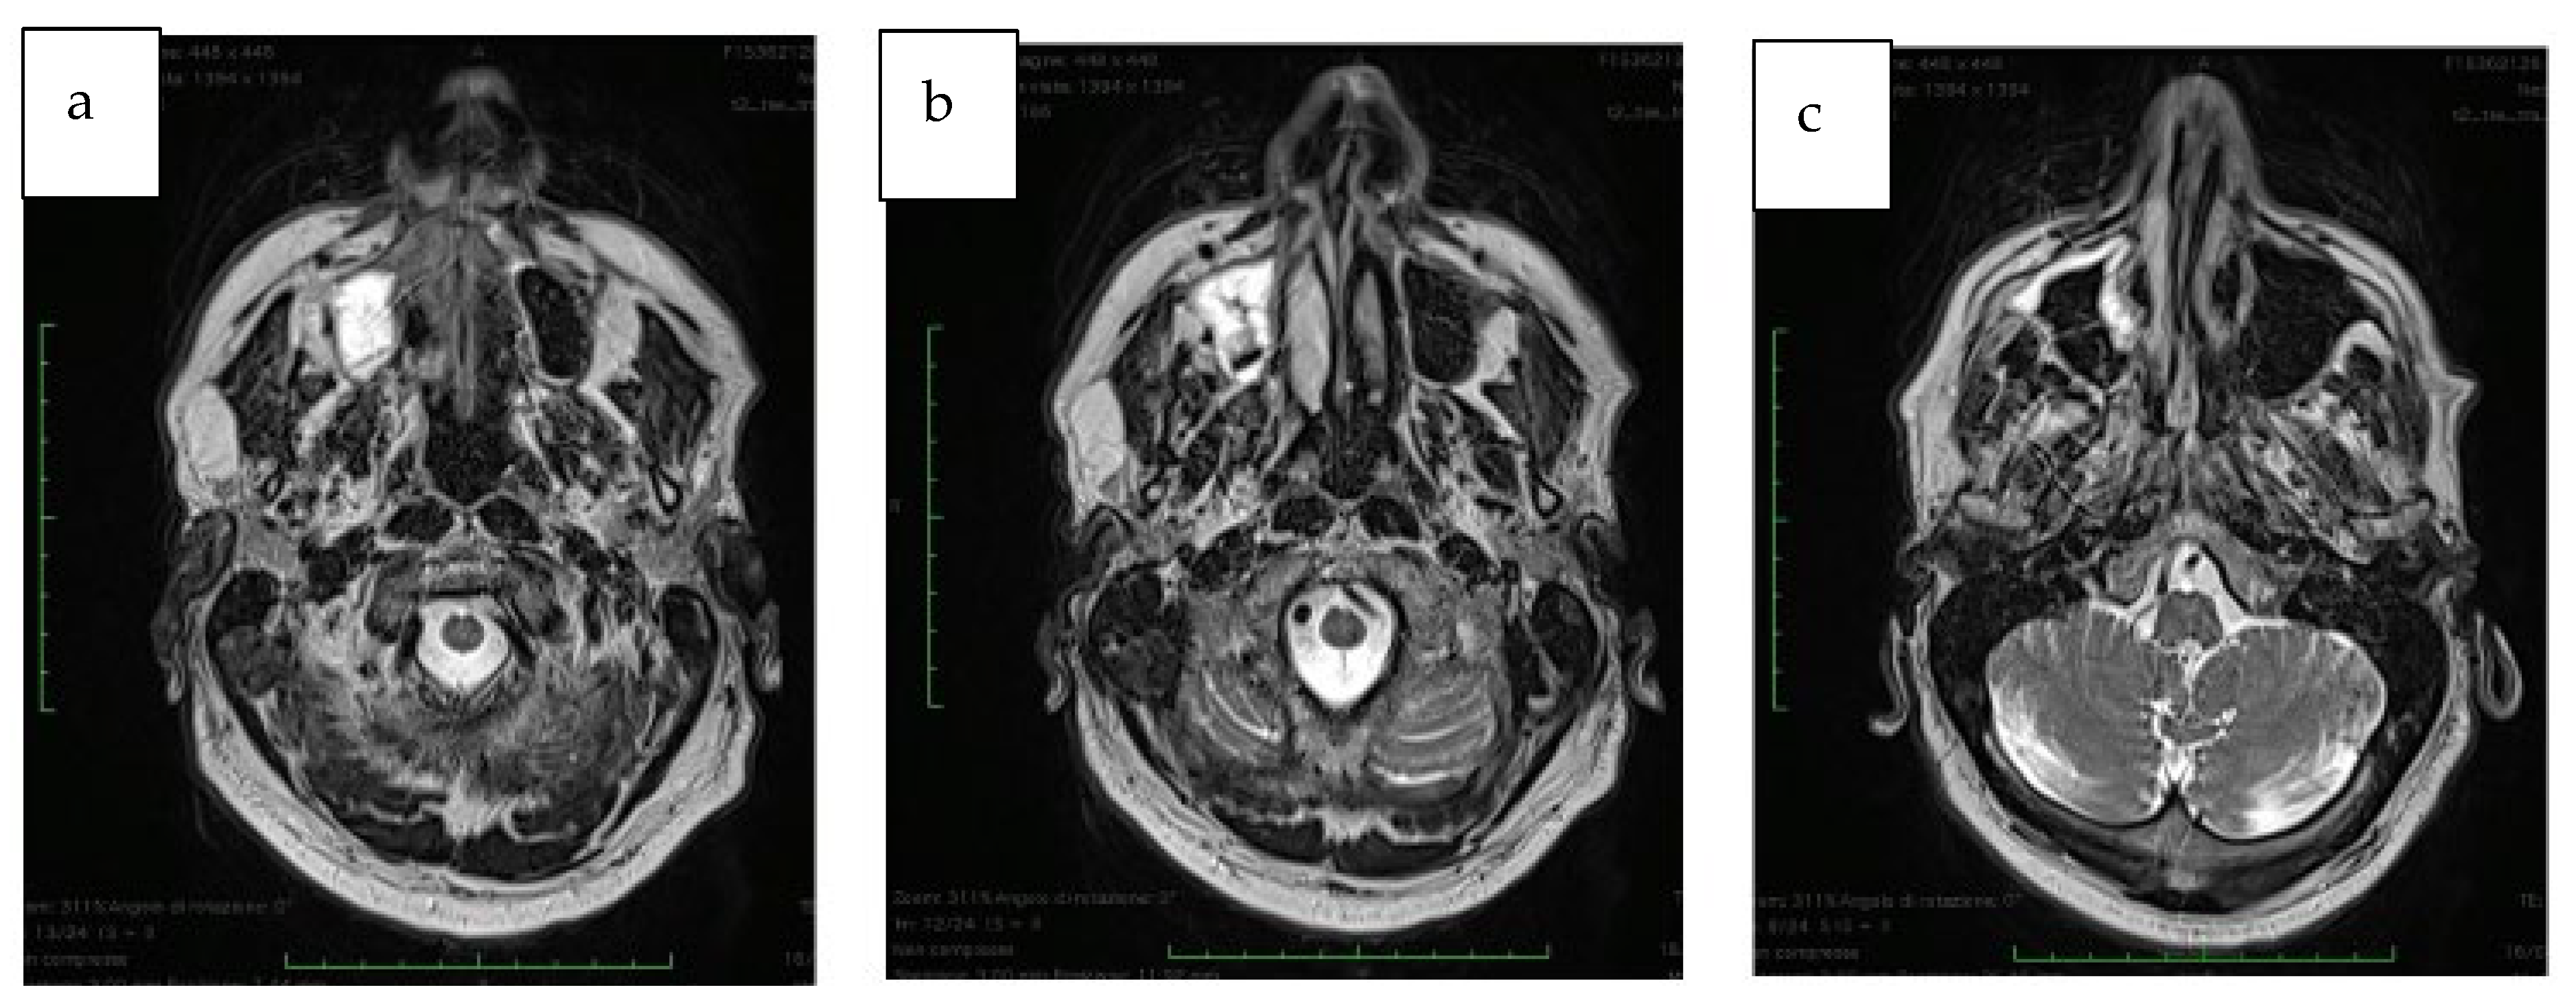

3.1. Detailed Medical History

3.2. Preoperative Oral Situation

3.3. Preoperative Protocol